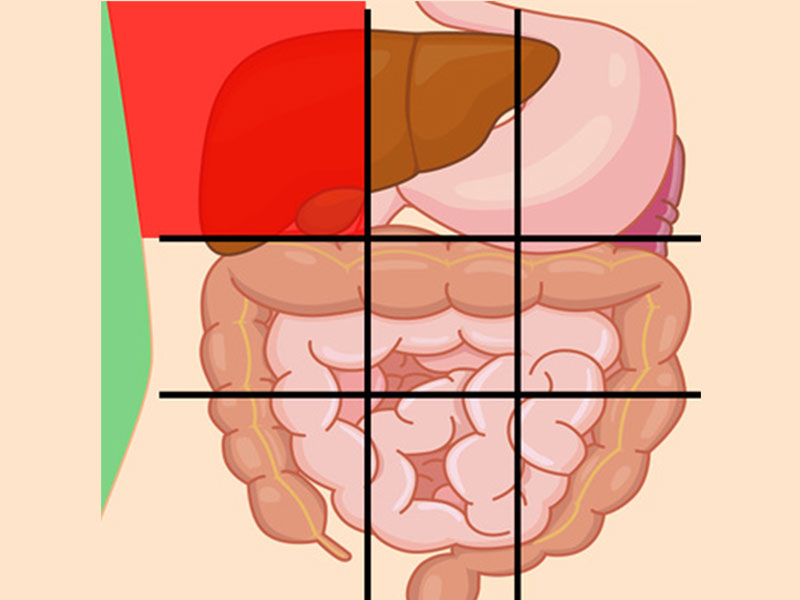

درد شکم در نواحی مختلف نشانه چیست؟

محل درد در شکم ممکن است سرنخی برای علت آن درد باشد که در زیر به بررسی آنها میپردازیم:

درد شکم سمت چپ بالا نشانه چیست؟

بخش اصلی معده انسان در سمت چپ شکم او قرار دارد همچنین قسمت بالایی سمت چپ شکم نزدیک به قلب است، بنابراین معمولاً احساس غیرمعمولی در این بخش نشاندهنده مشکل در این اندامها است.

علل عمده درد این ناحیه شامل:

- طحال بزرگشده

- انقباض مدفوع (مدفوع سفت شده که قابل دفع نیست)

- جراحت

- عفونت کلیه

- حمله قلبی

- سرطان

- التهاب معده

درد بالای شکم نشانه چیست؟

این ناحیه شامل لوزالمعده و بخشی از روده کوچک میباشد.

- پانکراتیک (التهاب لوزالمعده)

- فتق اپی گاستریک

- سنگهای صفراوی

- حمله قلبی

- هپاتیت (التهاب کبد)

- ذاتالریه